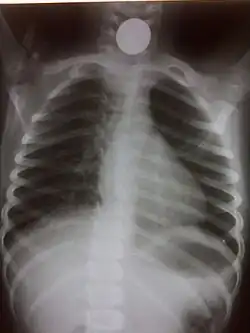

Chest radiograph showing a Venezuelan 25 cent coin lodged in the upper esophagus of a 9-year-old girl. -

A coin seen on AP CXR in the esophagus -

If the person who swallowed the foreign body is doing well, usually an x-ray image will be taken which will show any metal objects, and this will be repeated a few days later to confirm that the object has passed all the way through the digestive system. Also it needs to be confirmed that the object is not stuck in the airways, in the bronchial tree.